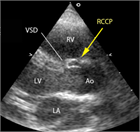

1. 心室中隔欠損は、欠損孔の部位により、膜性周囲部(perimembranous)、筋性部(muscular)、漏斗部または肺動脈弁下部(subarterial)に分類され、自然歴、手術適応が各々異なるため、部位診断は重要である。